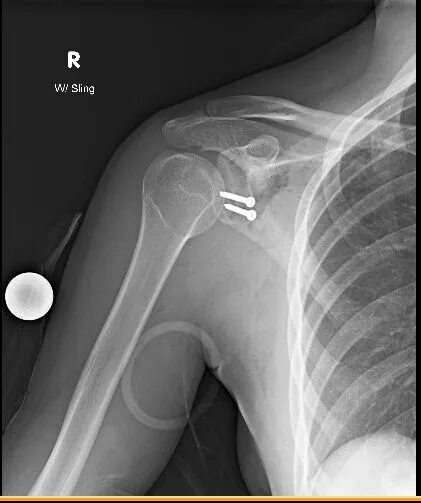

Как долго заживает вывих плеча